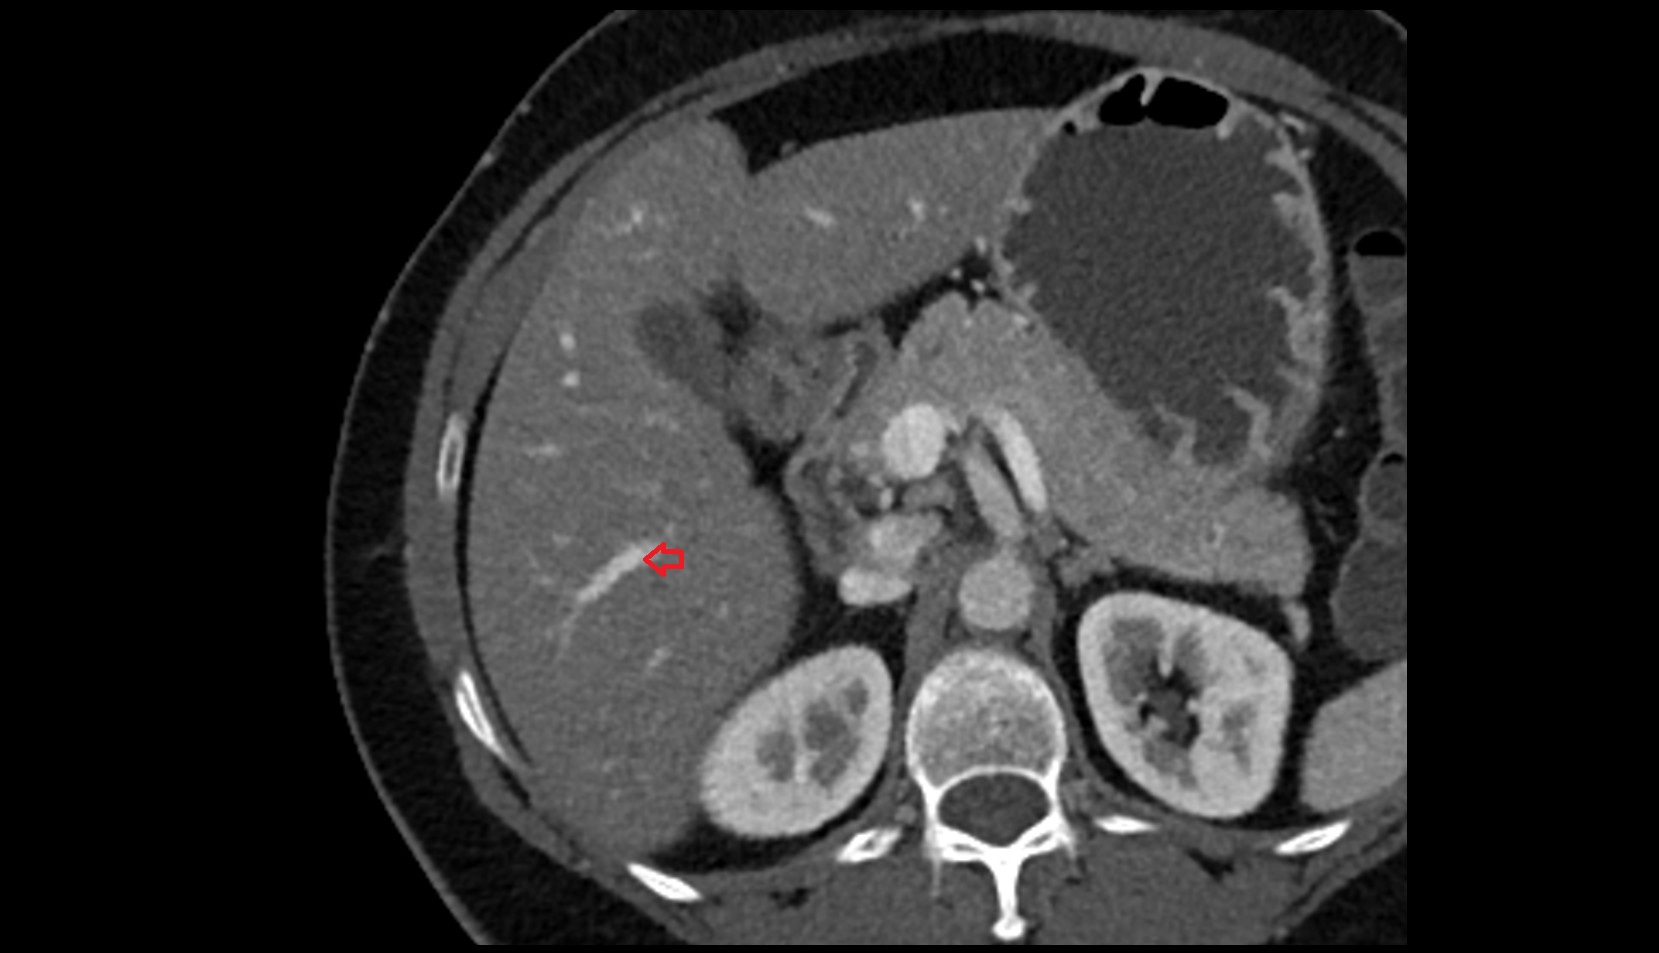

- Right lobe of liver

- Liver

- kidneys

- Right kidney

- Left kidney

- Liver Segment I – Caudate lobe

- Liver Segment V – Right anteroinferior segment

- Liver Segment VI – Right posteroinferior segment

- Liver Segment VII – Right posterosuperior segment

- Liver Segment VIII – Right anterosuperior segment